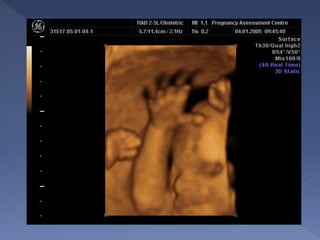

two-dimensional ultrasound (2D)

three and four-dimensional

ultrasound (3D/4D)